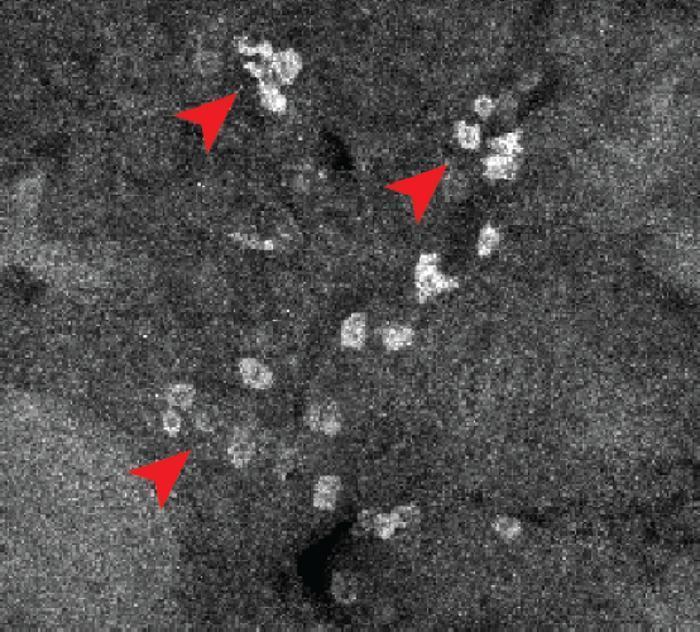

荧光成像显示伊布替尼在脾脏中结合。红色箭头表示伊布替尼阳性细胞。图片来源:美国斯克里普斯研究所

在验证实验中,他们绘制了抗癌药物伊布替尼和阿法替尼的结合图谱。结果显示,伊布替尼不仅与血细胞中的目标结合,还会与肝脏、心脏组织和血管中的免疫细胞结合,这为其可能引起心律不齐和出血的副作用提供了合理解释。